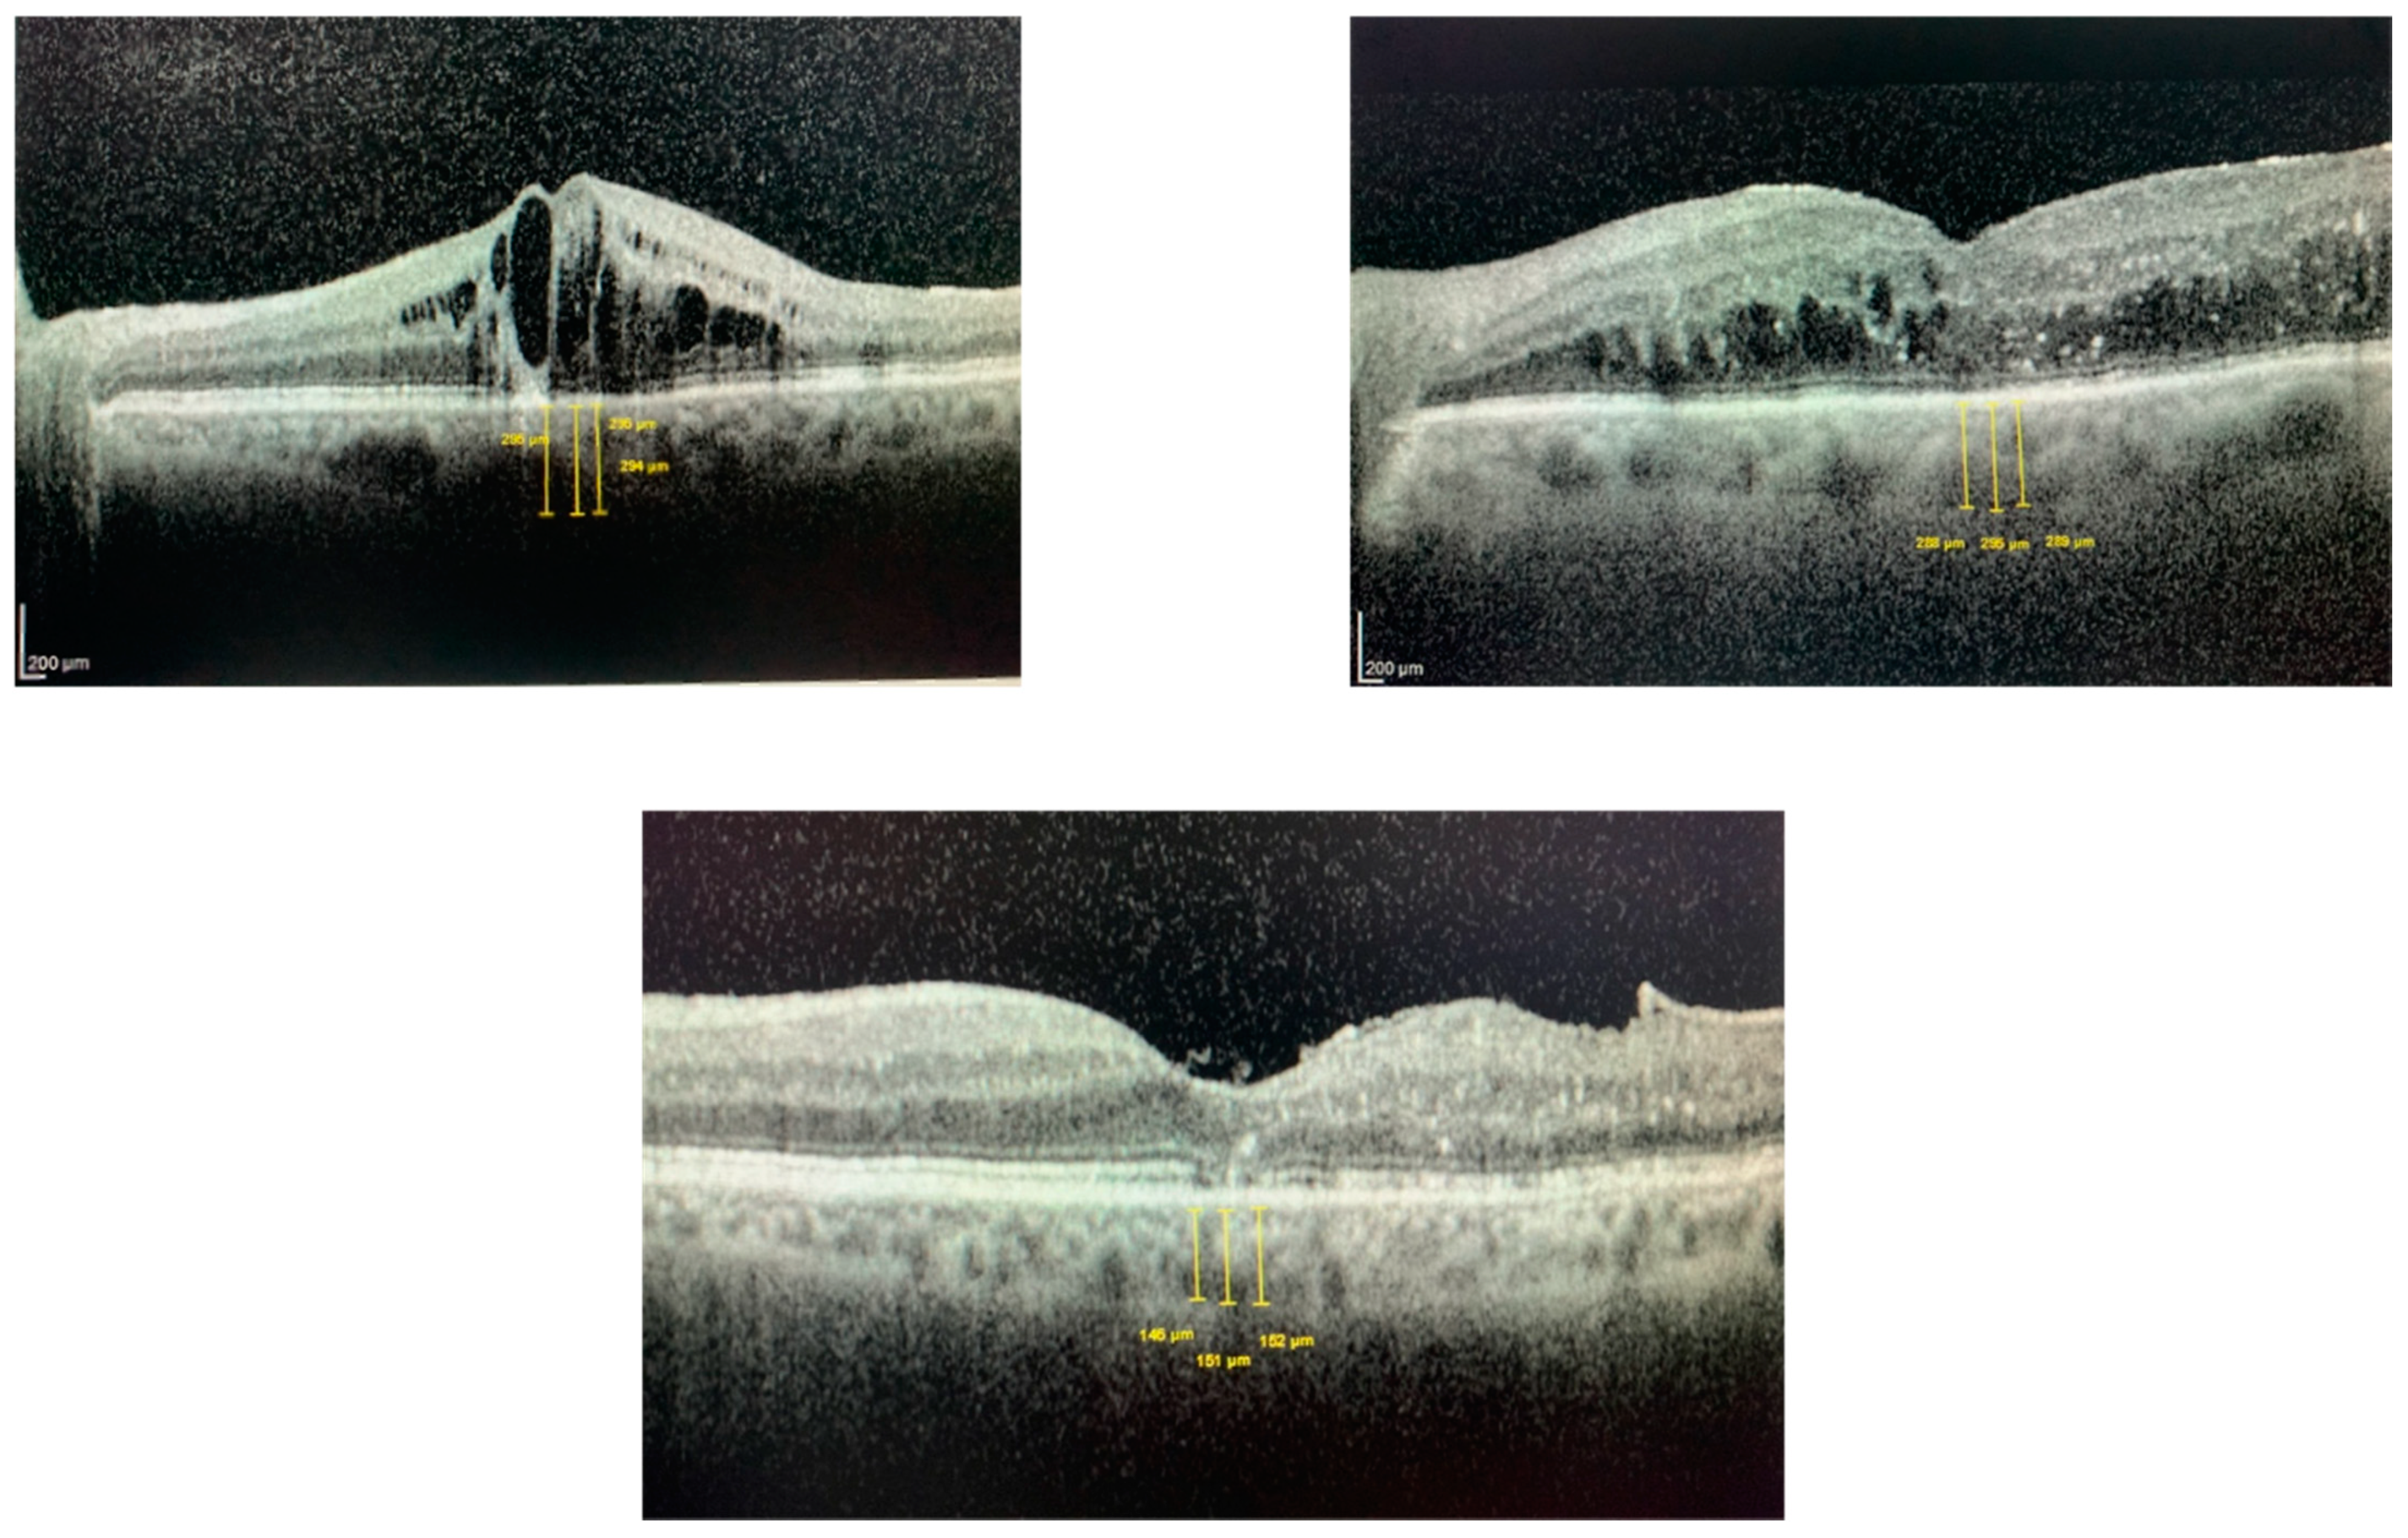

| Pre-treatment | 441.4 ± 75.9 μm | 274.7 ± 88.8 μm | 480.1 ± 97.3 μm | 291.6 ± 87.1 μm | |

| Post-treatment | 357.8 ± 87.2 μm | 235.6 ± 83.4 μm | 328.0 ± 72.2 μm | 229.8 ± 58.8 μm | |

| p-value | p < 0.001 | p < 0.001 | p < 0.001 | p < 0.001 | p = 0.022 |